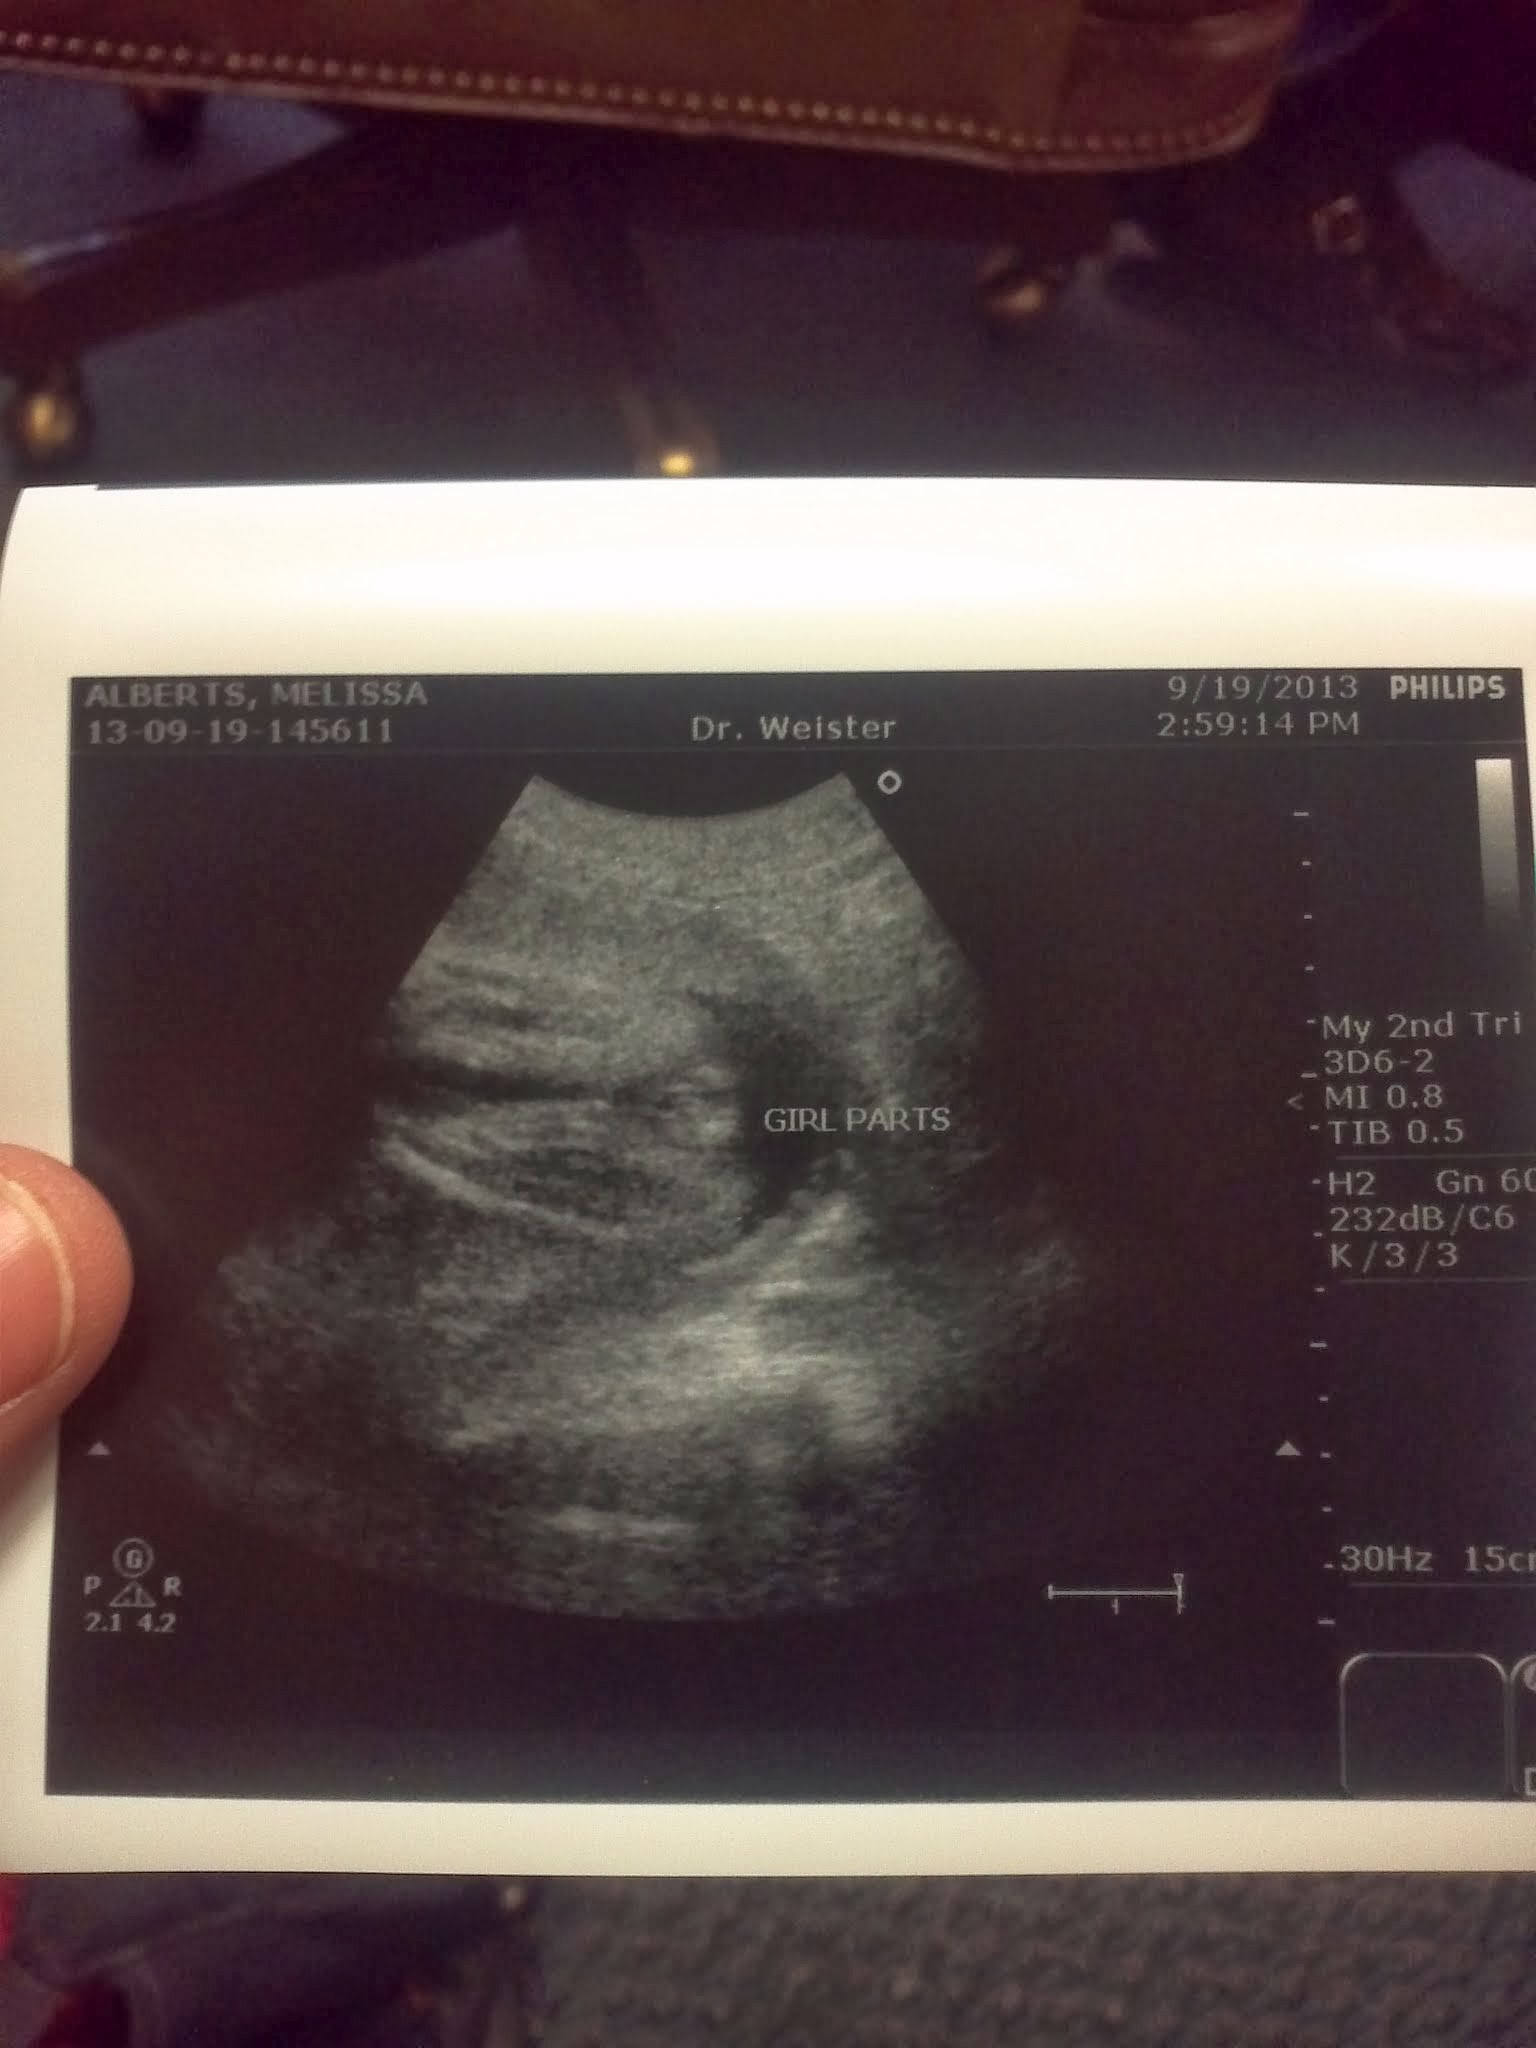

- We also had an ULTRASOUND!!! If you click on one of the pictures you will see the funny description of the way the doctor told us whether it was a girl or boy! He was a nice enough guy but I think he might hate his job… just the vibe we got. It’s either that or the fact that we were in a small room and I haven’t taken my monthly shower :-D.

Loved the bit about “girl parts”! When the ultrasound tech told us Sabin was a boy she used the term “boy bits” every time. I just thought it was kind of funny that they use all the clinical terms for the female anatomy every day but the fetus on the screen has “boy bits”.